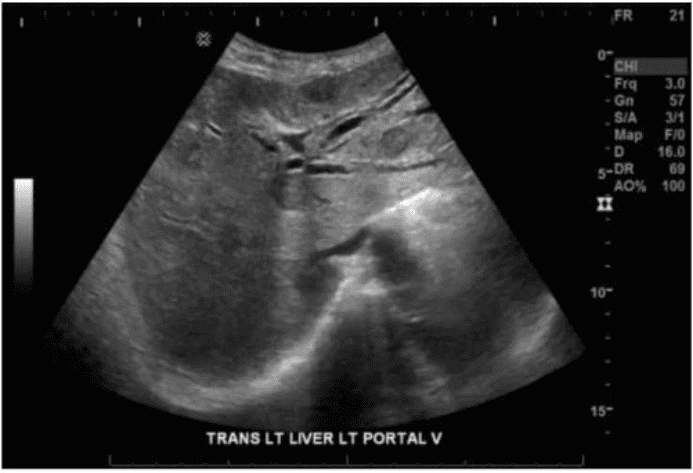

Which sonographic appearance of the bile ducts is demonstrated in this image?

How are portal veins differentiated from hepatic veins?